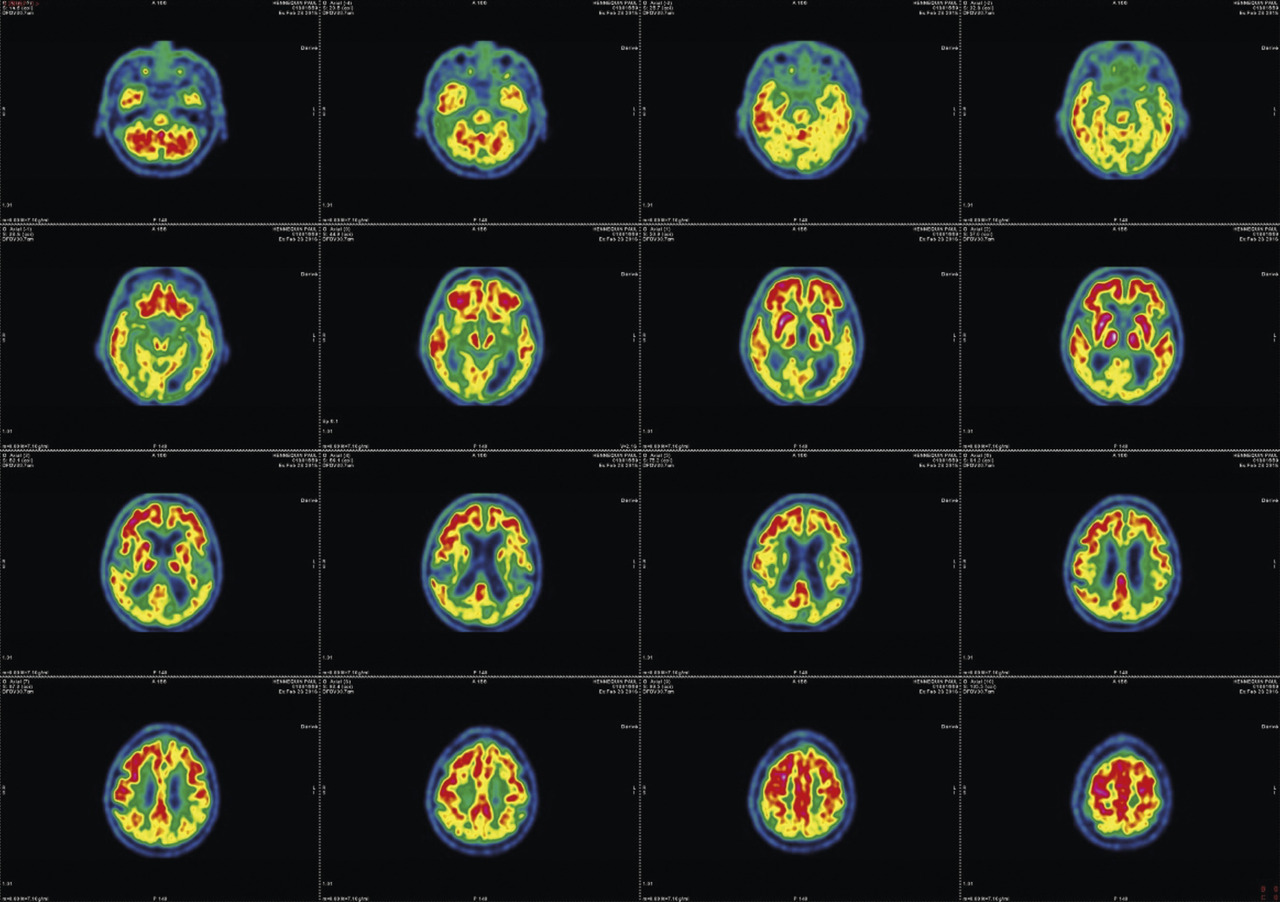

L’imagerie cérébrale morphologique et fonctionnelle (fig. 2-7) occupe une place prépondérante dans la recherche d’arguments en faveur d’une pathologie neurométabolique (maladie de Wilson chez les sujets jeunes), de lésions vasculaires ou d’une hydrocéphalie à pression normale. L’IRM cérébrale permet également de mettre en évidence des anomalies évocatrices de certains syndromes parkinsoniens dégénératifs.

Les progrès de l’imagerie fonctionnelle apportent une aide au diagnostic.